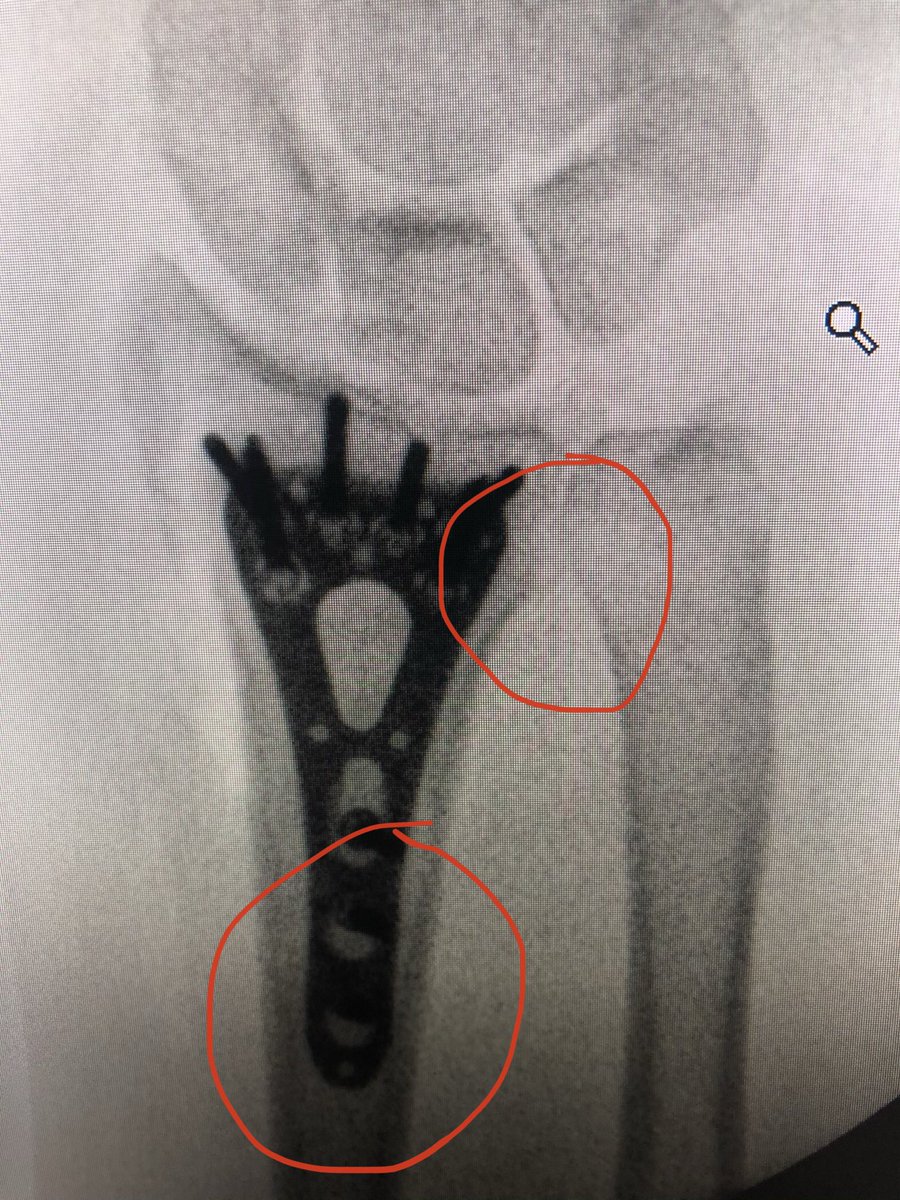

The lamina spreader goes in with the oblong hole cortical screw loosened a couple turns, this corrects alignment, tighten the screw and place more proximal locking screws to โ€˜fixโ€™ the plate position now. Inclination, DRUJ and plate position are corrected.

Check 20 degrees elevated lateral view to see safety of the joint and DRUJ view to make sure no screws violate DRUJ or are too long dorsally.